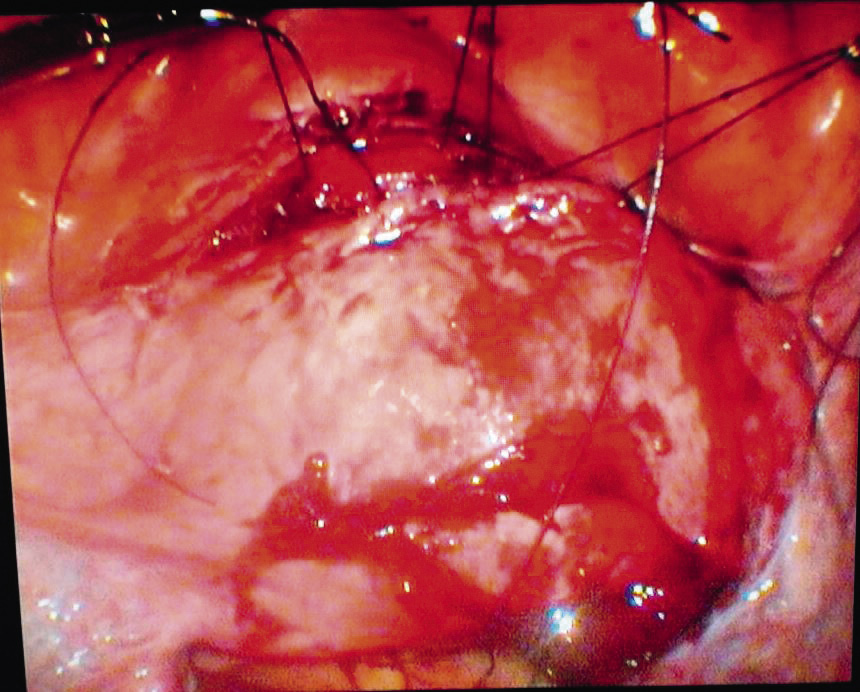

- сопоставление краев стенки матки двухрядными швами с последующим цервико- и гистероскопическим контролем (рис. 7);

Рис. 7. Сопоставление краев стенки матки отдельными двухрядными швами